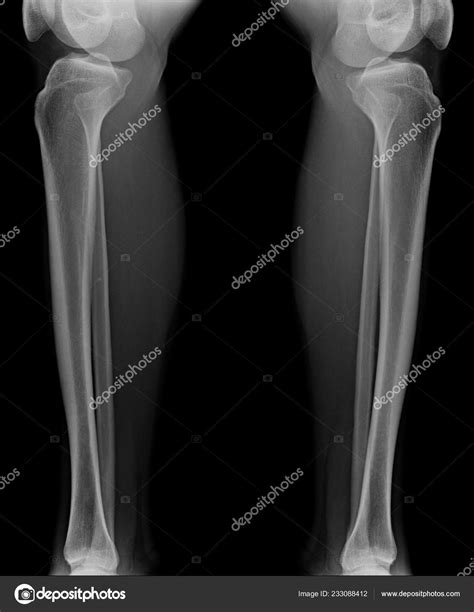

Diagnosing issues within the tibia a fibula complex typically begins with a physical examination and imaging studies. Physicians rely heavily on diagnostic tools to determine the severity of an injury and the appropriate path forward.

Common diagnostic methods include:

• X-rays: The gold standard for identifying fractures and checking alignment of the bones.

• MRI: Useful for detecting stress fractures that may not appear on an X-ray, as well as evaluating soft tissue, ligaments, and tendons.

• CT Scans: Used when more detailed images of the bone structure are needed, especially in complex, comminuted fractures.